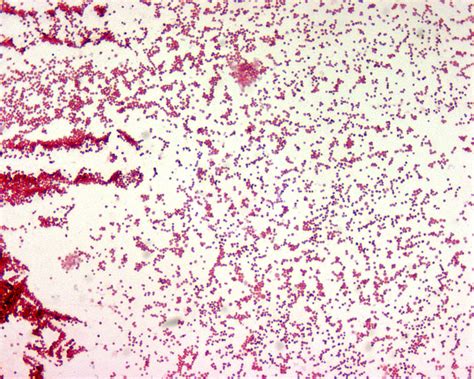

Salmonella Paratyphi Gram Stain | Smear made from a liquid culture (tryptic soy broth). Gram negative coccobacilli with bipolar staining; Salmonella enteritidis (salmonella enterica ssp.enterica, serotype enteritidis) micrograph. Gram stain is not a simple stain because simple stains do not use two or more stains. Salmonella typhi and paratyphi breach the intestinal barrier though specialized microfold cells (m cells) that transport the bacteria across the.

Gram staining is the most important and widely used differential staining technique in bacteriology. Used for selective recovery of salmonella from stool culture. A salmonella sample can be obtained directly from the patient. Smear made from a liquid culture (tryptic soy broth). In current study salmonella paratyphi was identified through differential medium, gram staining and different biochemical tests like imvic, catalase.

Salmonellosis (subtype typhimurium), typhoid fever (subtype typhi), and paratyphoid fever (subtype paratyphi a). Gram stain is not a simple stain because simple stains do not use two or more stains. Salmonella typhi in gram stain. Salmonella typhimurium (salmonella enterica subsp. A salmonella sample can be obtained directly from the patient. Gram negative coccobacilli with bipolar staining; Used for selective recovery of salmonella from stool culture. Salmonella is gram negative bacterium and causes intestinal diseases in all types of chickens. Most common cause of wound infections after dog or cat bites (pasteurellosis) salmonella enterica spp. These include salmonella enteritidis, salmonella paratyphi, salmonella typhi and salmonella typhimurium (even though they have been classed as serotypes). Enterica is the type species and is further divided into six subspecies that include over 2. Paratyphi b have been shown to live and multiply in sewage sludge at about 10 microscopy with gram stain. Salmonella gram stain typhi negative enterica microscope under rods structure electron antigenic scanning.